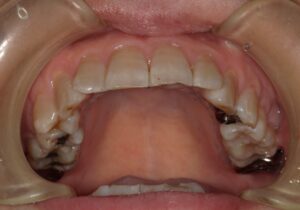

初診時54歳女性 体に不調を感じるとのことでした。夜間熟睡ができない。若い時は肩こりや頭痛もあった。左でよく噛んでいる。ということでした。口腔内を拝見すると下の前歯の真ん中が少し左にずれていました。かみ合わせた時に下の前歯は上の前歯に少し覆われるのが一般的なのですが、半分以上隠れています。歯科用語では過蓋咬合と言います。かみ合わせた時に下の前歯が上の前歯で完全に覆われている方もいらっしゃいます。下の前歯の付け根当たり、犬歯がわかりやすいかもしれません。骨がもっこりしているように見えます。かみ合わせが強い方によく見られます。骨隆起と言います。上の真ん中から3番目の犬歯が一つ後ろの歯に比べて内側に傾斜しています。

前歯4本が直線的に並んでいます。真ん中から2つ目と3つ目の間に段差がついているような感じです。顎が少し小さくて歯が並ぶだけの大きさになっていないようです。